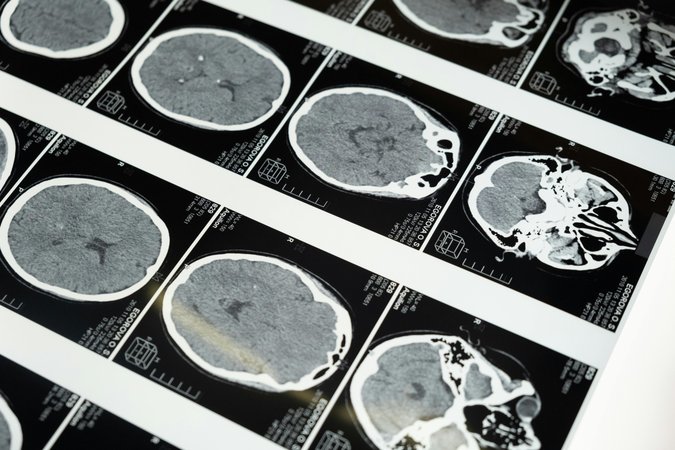

2. 뇌 자기공명영상(MRI) 촬영

소뇌 위축 정도와 다른 신경계 이상 여부를 확인합니다.